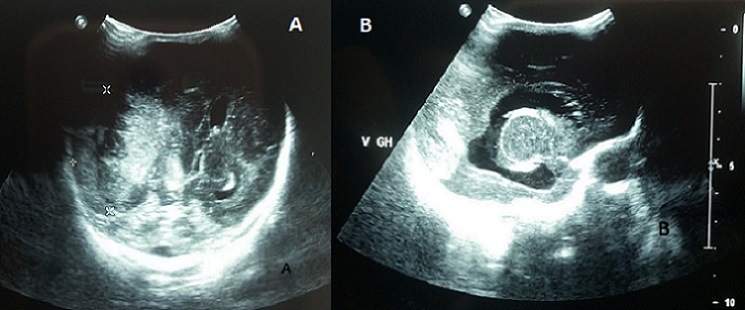

Epidural hematoma in newborns is rare, it occurs more frequently in infants born from nulliparous mothers with delivery difficulties. Intracranial hemorrhage in infants is usually secondary to vascular malformations, anticoagulation, inherited or acquired coagulopathy. Hematological disorders are infrequently associated with congenital rubella. The main defects of the disease associate deafness, cataracts, congenital heart disease, microcephaly and mental retardation. Rubella remains a public health problem in developing countries, in which rubella immunization is not a part of the national immunization program. We report a preterm infant, born at 31 weeks of gestation, by caesarean section for fetal distress. Prenatal ultrasound showed intrauterine growth restriction with marked oligohydramnios. The mother reported pyrexia and rush in the first missed menstrual period. Maternal rubella status was unknown. At birth, clinical examination showed microcephaly, blueberry muffin rash, diffused ecchymoses, splenomegaly, jaundice, lethargy, hypotonia and mutisite bleeding. Laboratory tests showed severe thrombocytopenia at 8 x 109/L, prolonged prothrombin time, anemia at 10.2g/dL, and hyperbilirubinemia. Urgent cranial ultrasound showed epidural hematoma with mass effect on the underlying parietal lobe and the right lateral ventricle with mid-line shift (A). It also revealed hydropcephaly sequelae of prenatal intraventricular hemorrhage; with periventricular cysts and thalamic arteritis, signs of fetopathy (B). Congenital rubella syndrome diagnosis was confirmed by a positive test of specific anti-rubella immunoglobulins M. The outcome was poor with persistence of disseminated intravascular coagulation requiring multiple fresh frozen plasma and platelet transfusion. The infant died on the third day of life secondary to refractive hemorrhage.